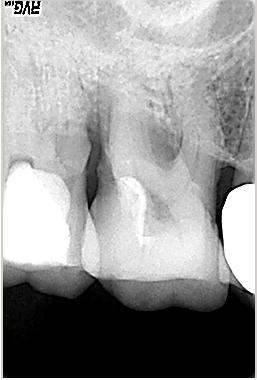

Röntgenologischer Ausgangsbefund im Febr. 2003 mit caries profunda, starken Krümmungen sowohl der mesiobuccalen wie auch der distobuccalen Wurzeln